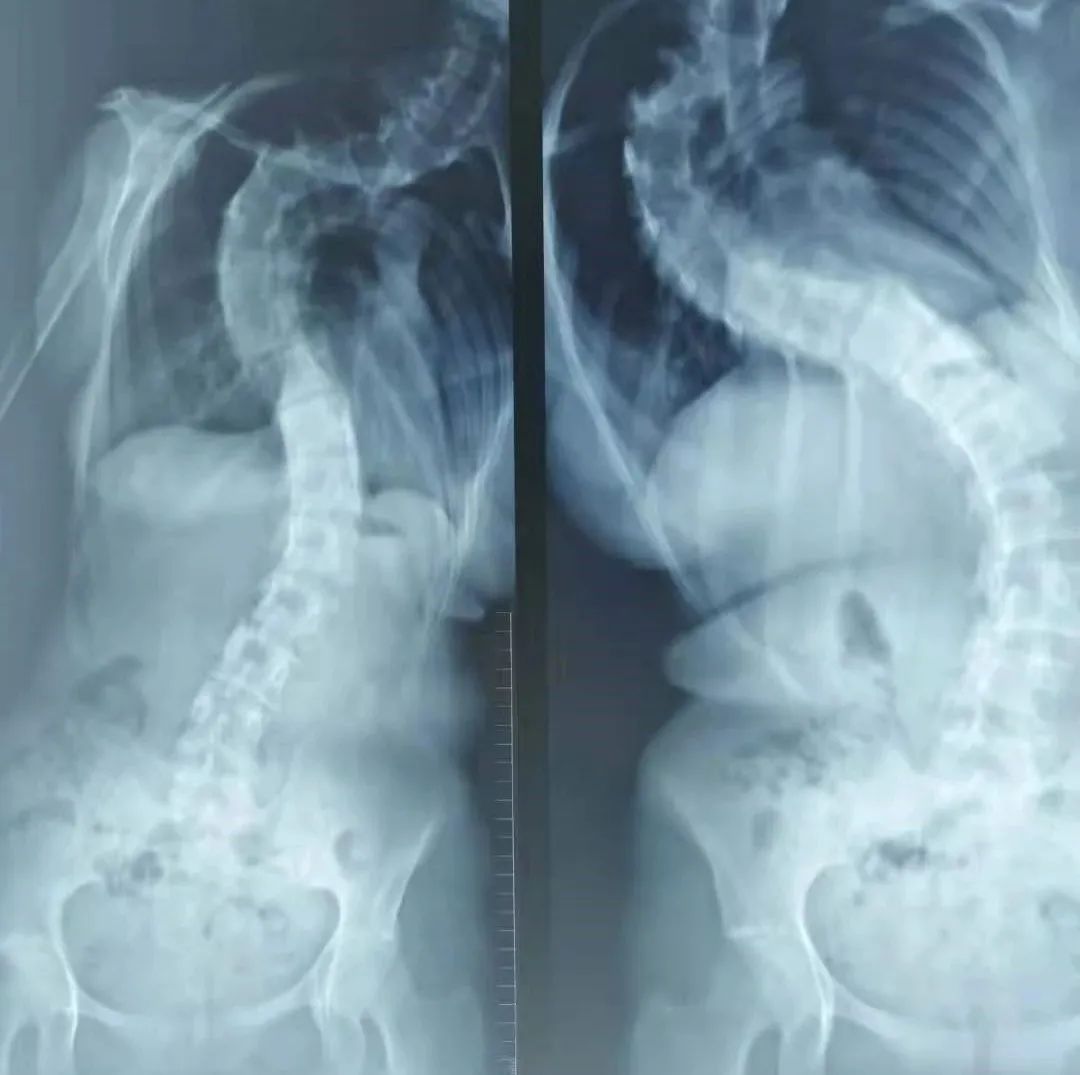

在啟動(dòng)儀式進(jìn)行的同時(shí),北京協(xié)和醫(yī)院骨科王升儒教授、北京協(xié)和醫(yī)院中國康復(fù)醫(yī)學(xué)會(huì)脊柱脊髓專業(yè)委員會(huì)神經(jīng)電生理學(xué)組副主任委員王樹杰教授,為一名低收入家庭高難度脊柱側(cè)彎青少年的手術(shù)進(jìn)行術(shù)前準(zhǔn)備。隨后,由北京協(xié)和醫(yī)院骨科主任仉建國教授團(tuán)隊(duì)和山西白求恩醫(yī)院同濟(jì)山西醫(yī)院骨科主任馮皓宇教授團(tuán)隊(duì)共同實(shí)施了矯治手術(shù)?;颊咭虿⌒輰W(xué),且由于費(fèi)用問題一直未進(jìn)行治療。此次公益行動(dòng),各位專家放棄休息時(shí)間為患兒解決疾患,并由基金會(huì)對患者進(jìn)行一定金額的手術(shù)資助,術(shù)后患者也能在當(dāng)?shù)亟邮苤委熀碗S訪,緩解了家庭經(jīng)濟(jì)壓力,重新建立自信,重塑“挺拔人生”。

患者術(shù)前圖片